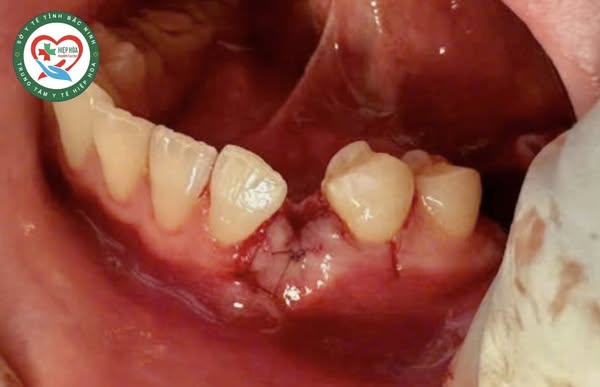

Bệnh nhân được chỉ định phẫu thuật loại bỏ khối u răng. Sau hơn 1 giờ, kíp phẫu thuật do Bs. Đào Thị Ngọc mai, bác sĩ chuyên khoa Răng - Hàm - Mặt, cùng thành viên ê kíp phẫu thuật đã phẫu thuật loại bỏ khối u răng đa hợp R33 cho bệnh nhân. Trong quá trình phẫu thuật, các bác sĩ lấy ra 12 chiếc răng nhỏ tại khối u có đầy đủ thân, tủy và chân răng. Bệnh nhân được phẫu thuật lấy U trên ghế nha khoa dưới gây tê tại chỗ và kiểm soát hành vi.

Hình ảnh 12 chiếc răng lấy từ trong khối u ra.